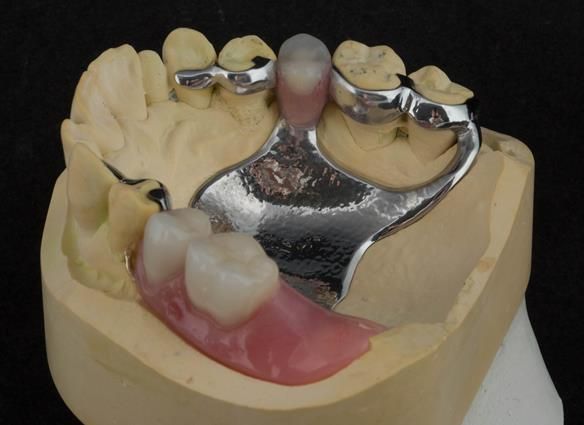

This newsletter describes in step by step detail Angela's transition through immediate partial dentures to crown supported definitive metal based dentures.

The clinical situation and treatment process is shown in detail below with photographs. I (Finlay Sutton) provided the clinical work and Rowan Garstang provided the technical work.